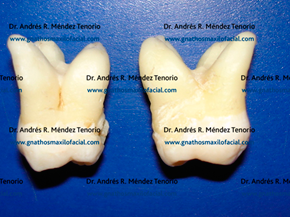

| 3er molar superior derecho con la capsula del quiste |

El 3er molar es una pieza dentaria que tiene gran cantidad de variaciones anatómicas, de posición y de número. Por lo que se pueden encontrar molares con 4 raíces separadas o fusionadas, en posición horizontal, angulado o invertido. Incluso existen los 3os molares supernumerarios en proximidad con los 3os molares.

| 3os molares con cuatro raíces separadas | |